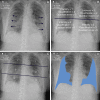

Background Radiographic severity may help predict patient deterioration and outcomes from COVID-19 pneumonia. Purpose To assess the reliability and reproducibility of three chest radiograph reporting systems (radiographic assessment of lung edema [RALE], Brixia, and percentage opacification) in patients with proven SARS-CoV-2 infection and examine the ability of these scores to predict adverse outcomes both alone and in conjunction with two clinical scoring systems, National Early Warning Score 2 (NEWS2) and International Severe Acute Respiratory and Emerging Infection Consortium: Coronavirus Clinical Characterization Consortium (ISARIC-4C) mortality. Materials and Methods This retrospective cohort study used routinely collected clinical data of patients with polymerase chain reaction-positive SARS-CoV-2 infection admitted to a single center from February 2020 through July 2020. Initial chest radiographs were scored for RALE, Brixia, and percentage opacification by one of three radiologists. Intra- and interreader agreement were assessed with intraclass correlation coefficients. The rate of admission to the intensive care unit (ICU) or death up to 60 days after scored chest radiograph was estimated. NEWS2 and ISARIC-4C mortality at hospital admission were calculated. Daily risk for admission to ICU or death was modeled with Cox proportional hazards models that incorporated the chest radiograph scores adjusted for NEWS2 or ISARIC-4C mortality. Results Admission chest radiographs of 50 patients (mean age, 74 years ± 16 [standard deviation]; 28 men) were scored by all three radiologists, with good interreader reliability for all scores, as follows: intraclass correlation coefficients were 0.87 for RALE (95% CI: 0.80, 0.92), 0.86 for Brixia (95% CI: 0.76, 0.92), and 0.72 for percentage opacification (95% CI: 0.48, 0.85). Of 751 patients with a chest radiograph, those with greater than 75% opacification had a median time to ICU admission or death of just 1-2 days. Among 628 patients for whom data were available (median age, 76 years [interquartile range, 61-84 years]; 344 men), opacification of 51%-75% increased risk for ICU admission or death by twofold (hazard ratio, 2.2; 95% CI: 1.6, 2.8), and opacification greater than 75% increased ICU risk by fourfold (hazard ratio, 4.0; 95% CI: 3.4, 4.7) compared with opacification of 0%-25%, when adjusted for NEWS2 score. Conclusion Brixia, radiographic assessment of lung edema, and percentage opacification scores all reliably helped predict adverse outcomes in SARS-CoV-2 infection. © RSNA, 2021 Online supplemental material is available for this article. See also the editorial by Little in this issue.